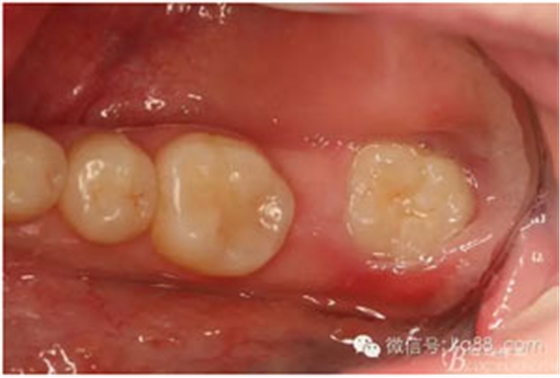

圖2.術(shù)前口內(nèi)照:37未萌出。38牙冠近中傾斜?;颊哒衬ど珴烧#瑹o瘺管、無滲出。